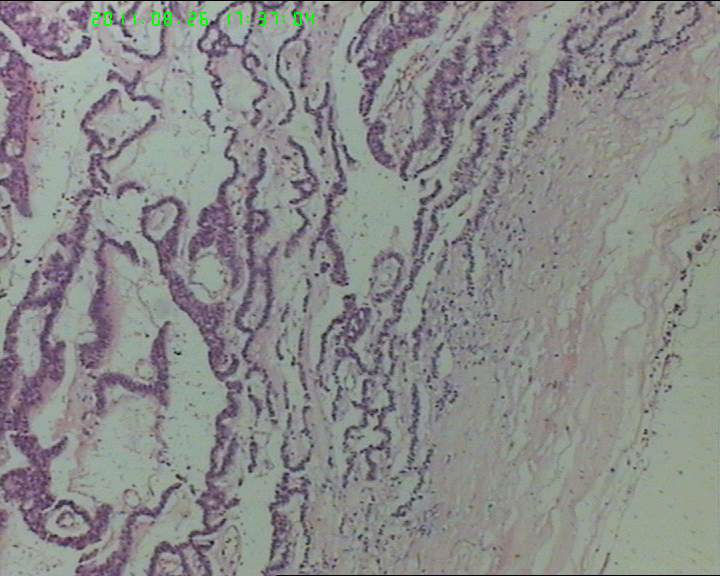

76岁女性卵巢巨大囊性肿物

卵巢肿物,大小18*14*10cm

此3张图片为宫颈处组织

支持细胞瘤,伴性索分化的生殖细胞肿瘤,类癌,转移性腺癌

类癌